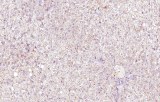

Primary antibodies for immunohistochemistry CE/IVD - Pediatric pathology

Perinatal/paediatric pathology is a medical subspecialty with particular expertise in diseases affecting the placenta, fetus, infant and child. Although many conditions that affect adults also affect children, pediatric pathology includes many conditions found only in patients younger than 18 years of age. One group of conditions involving the infant population is congenital anomalies. A malformation is a congenital anomaly due to an intrinsic defect in development. A disruption occurs when a normally developing organ is secondarily damaged by another process. A sequence is a collection of several anomalies, all of which are due to one malformation, disruption, or deformation. Finally, a syndrome is a group of related anomalies. An other group is the pediatric cancers or childhood cancers. Childhood cancers include many that also occur in adults. Leukemia is by far the most common, representing about 33% of childhood cancers, brain tumors represent about 25%, lymphomas represent about 8%, and certain bone cancers (osteosarcoma and Ewing sarcoma) represent about 4%.